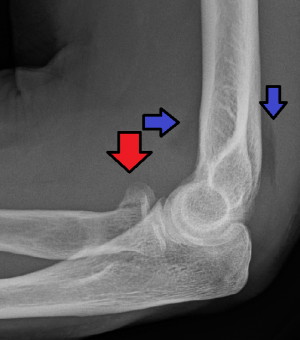

Radial head fracture (red arrow) with posterior and anterior sail sign (blue arrows).

- AP and lateral elbow xray

- Assess for anterior fat pad